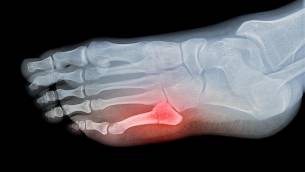

Krankengymnastik nach einem Mittelfußbruch Bei einem Mittelfußbruch handelt es sich um eine Fraktur im Bereich der Mittelfußknochen, den Metatarsalknochen Es kann dabei zum Bruch eines einzigen oder aber auch mehrerer der 5 Metatarsalknochen kommen. Nach Verordnung beginnen Verwandte Fragen Muss ich eine Zuzahlung für Krankengymnastik, Massagen oder andere Heilmittel leisten?. Nach der Operation eines Sprunggelenkbruchs kann es kurzfristig Vorteile haben, eine abnehmbare Bandage oder Schiene zu tragen und bereits nach einigen en vorsichtig mit Bewegungsübungen oder Physiotherapie zu beginnen Zu frühe Bewegung kann aber auch zu Problemen bei der Wundheilung führen.

In Lorsch erhalten Sie bei einem Mittelfußbruch eine vollumfängliche Behandlung In unserer orthopädischen Notaufnahme sind wir bereits unmittelbar nach dem Unfall für Sie da und versorgen Sie weiter Unsere Experten unterstützen Sie dabei, wieder möglichst schnell in Ihren (Sport) Alltag zurück zu finden. Nach einem glatten Ermüdungsbruch vor 9 Wochen (Vacopedes Schuh), darf ich seit gestern meinen Fuß wieder normal belasten Musste mir Trekkingsandalen mit diversen Klettverschlüssen kaufen in die ich meine Einlagen intigrieren kann. Der Mittelfußbruch macht etwa ein Drittel aller Fußbrüche aus, wobei meist Sportler davon betroffen sind Am häufigsten ist der fünfte Mittelfußknochen gebrochen Die Mittelfußknochen werden systematisch von innen nach außen durchnummeriert (Metatarsalia I bis V), wobei der erste Mittelfußknochen mit der großen Zehe verbunden ist.